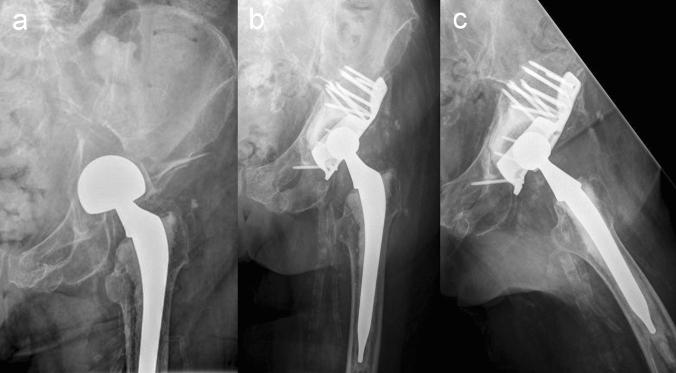

Open reduction and internal fixation is considered the gold standard of treatment for displaced acetabular fractures in younger patients. For elderly patients with osteoporotic bone quality, however, primary total hip arthroplasty (THA) with the advantage of immediate postoperative mobilization might be an option. The purpose of this study was to evaluate the clinical and radiological outcomes of surgical treatment of displaced osteoporotic acetabular fractures using the acetabular roof reinforcement plate (ARRP) combined with THA.

Between 2009 and 2019, 84 patients were operated using the ARRP combined with THA. Inclusion criteria were displaced osteoporotic fractures of the acetabulum with or without previous hemi- or total hip arthroplasty, age above 65 years, and pre-injury ability to walk at least with use of a walking frame. Of the 84 patients, 59 could be followed up after 6 months clinically and radiographically. Forty-nine (83%) were primary fractures and 10 (17%) periprosthetic acetabular fractures.

The mean age was 80.5 years (range 65-98 years). The average time from injury to surgery was 8.5 days (range 1-28). Mean time of surgery was 167 min (range 100-303 min). Immediate postoperative full weight bearing (FWB) was allowed for 51 patients (86%). At the 6-month follow-up, all 59 patients except one showed bony healing and incorporation of the ARRP. One case developed a non-union of the anterior column. No disruption, breakage or loosening of the ARRP was seen. Additional CT scans performed in 18 patients confirmed bony healing. Twenty-six patients (44%) had regained their pre-injury level of mobility. Complications requiring revision surgery occurred in 8 patients. Five of them were suffering from a prosthetic head dislocation, one from infection, one from hematoma and one from a heterotopic ossification.

The ARRP has proven to provide sufficient primary stability to allow for immediate FWB in most cases and represents a valuable option for the surgical management of displaced acetabular fractures in this challenging patient group.